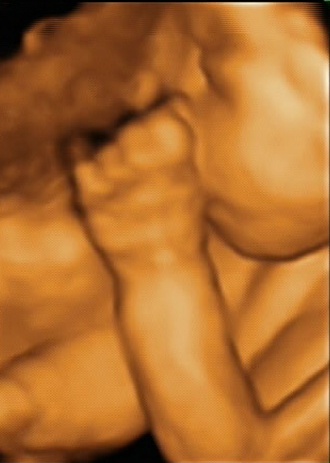

Ecografie

Ecografie (2D, 3D e

4D

) effettuate durante la gravidanza di Alice